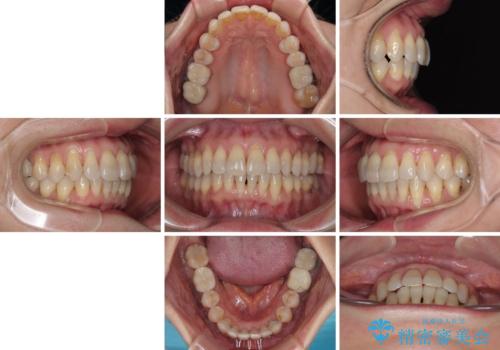

- 上下前歯のデコボコと、奥歯の銀歯を気にして来院された患者様です。

概ね歯列が整ったところで銀歯の全てをセラミッククラウンなどに置き換え、その後インビザラインを1セット使用して仕上げていくこととしました。

矯正治療の後半にはホワイトニングもされ、スッキリした口元に仕上げることができました。